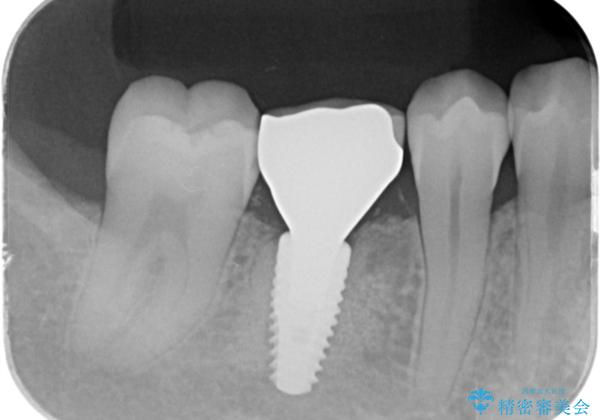

[ インプラント体・カスタムアバットメント・ジルコニアクラウン ] インプラントの構造

- インプラント治療は、歯を抜去し失ってしまった状態で咬合機能の回復をする治療です。

まず骨内にインプラント体を埋入し、クラウンとインプラント体をつなぐパーツ(アバットメント)、歯の形態を再現したクラウンの3つのパーツで構成されます。

今回は

ストローマン社製BLTインプラント

ジルコニアカスタムアバットメント(金属アレルギーのため)

ジルコニアクラウン

の3つの構成要素でインプラント治療を行っています。